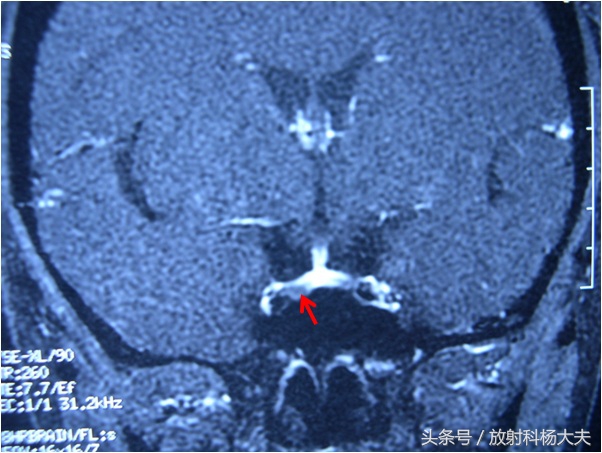

下图红箭所示的小黑点就是那个小瘤子,原来那个医院做的垂体MRI非常棒,做这种检查一定要做动态增强扫描,也就是打了药后不停地进行扫描,垂体瘤会在某一期,表现为低信号。这个扫描虽然不是什么高精尖的扫描技术,但也挺考验医院水平的,假如按照常规的扫描方法,很可能竹篮子打水一场空,瘤子明明就在那里,你却看不到。

杨大夫听了家属的介绍,又看了患者的MRI片子,这不就是我们常见的垂体瘤吗?而且患者的垂体瘤直径也不大,属于微腺瘤,连开刀都不用,只要吃点药控制住就可以了,听了杨大夫的话,小女孩终于鼓起勇气说,大夫,你能和我说说这瘤是怎么回事吗?